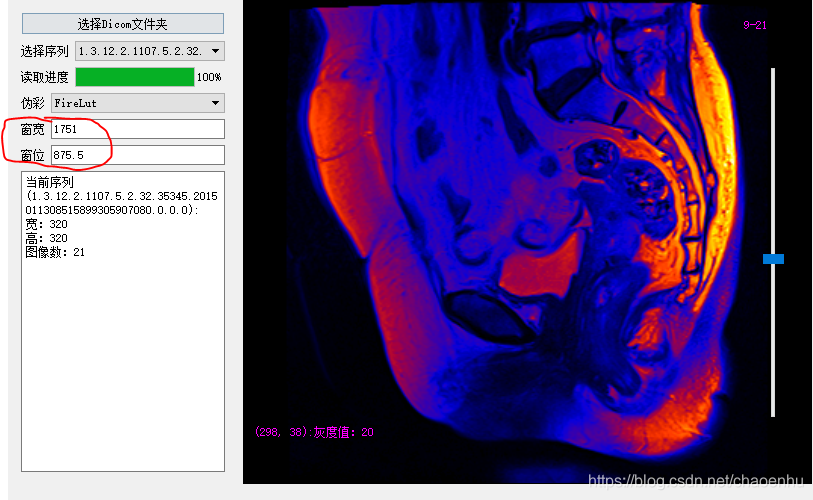

...运行调试,点击“选择Dicom文件夹”后

设置伪彩色

调整窗宽窗位:1)通过按住拖动鼠标右键;2) 修改窗宽窗位值;3) 按住鼠标左键划框(感兴趣区域);